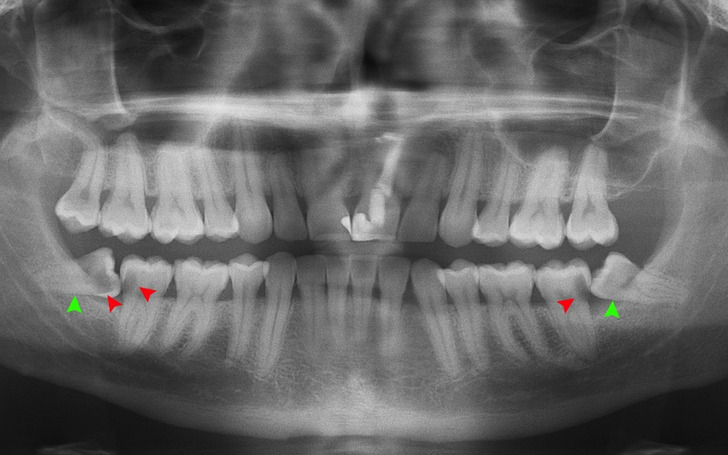

Entre 5% e 37% das pessoas sortudas já nascem sem os dentes do siso. Provavelmente, esses dentes estão deixando de se desenvolver por falta de necessidade, já que nossos ancestrais precisavam deles para mastigar alimentos mais duros e fibrosos, como raízes, folhas, nozes e carne.